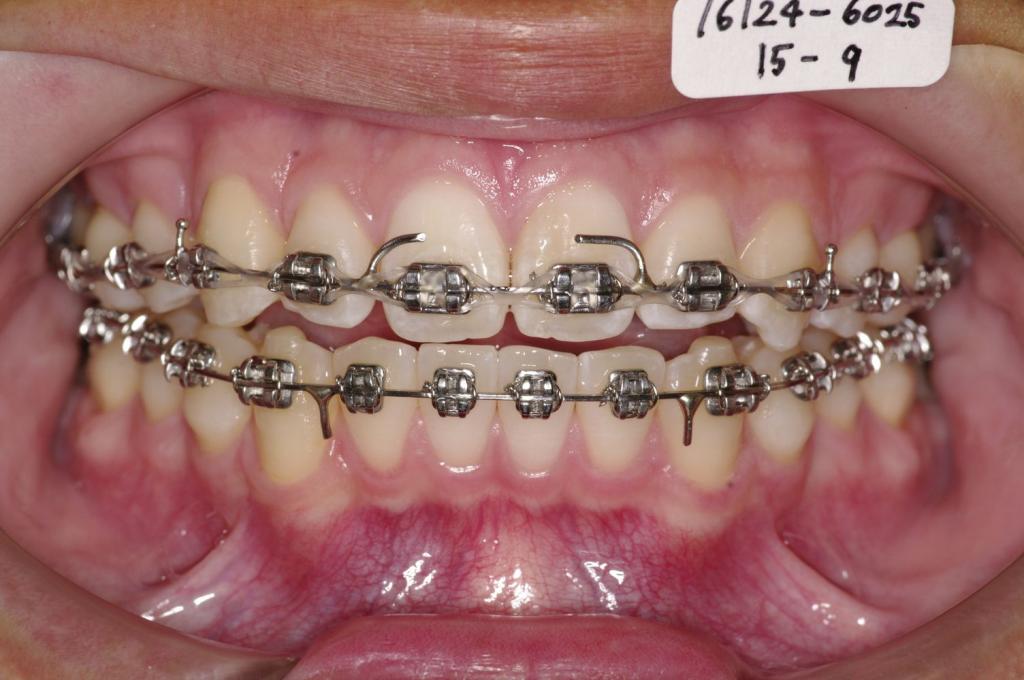

装置写真

治療前

前歯、出っ歯・開咬の矯正治療前口内写真NO.1102